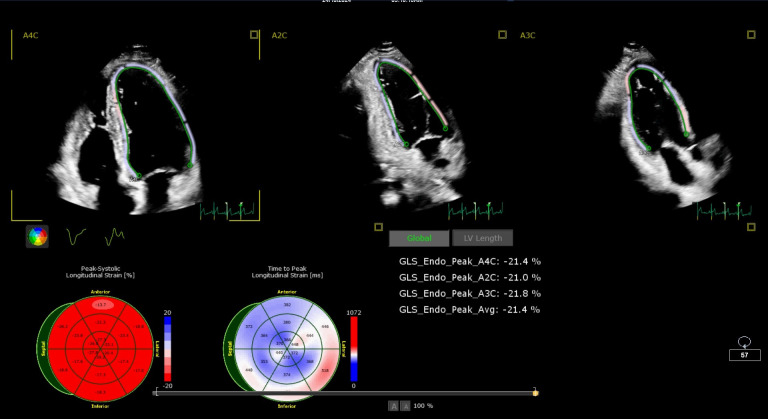

Background: Subclinical systolic dysfunction due to diabetic microangiopathy and its impact on left ventricular (LV) function remains unclear. Myocardial deformation (strain) imaging can detect LV systolic dysfunction earlier than conventional ejection fraction evaluations. Thus, this study aimed to examine the relationship between uncontrolled diabetes and impaired LV global longitudinal strain (GLS) in patients with diabetes mellitus (DM) compared to non-diabetic individuals.

Results: The absolute GLS% was significantly lower in the uncontrolled diabetic group (-18.4 ± 1.7) compared to controls (-22 ± 1.9, p < 0.001). Diabetic patients with complications had lower absolute GLS% values of -18.9 ± 1.7 for no complications, -17.5 ± 1.3 for one complication, and -16.8 ± 1.3 for two or more complications (p-value = 0.001). Regression analysis showed a positive association between complications and lower absolute GLS% (β = 0.41, p < 0.001). No significant difference was found in LV mass between hypertensive (155.1 ± 40.4) and non-hypertensive individuals (139.8 ± 44.3; p-value = 0.19).

Conclusion: Uncontrolled diabetes and the presence of complications were associated with lower absolute GLS% values, suggesting impaired myocardial deformation. These findings highlight the importance of monitoring GLS% as a potential marker for cardiac involvement in diabetic patients.